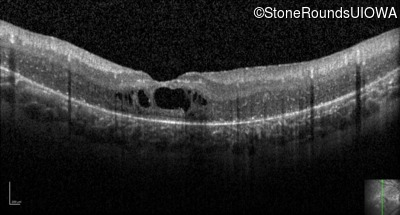

Optical Coherence Tomography - Right - 20/80

Exemplar / OCT Stack

Optical Coherence Tomography - Left - 20/200